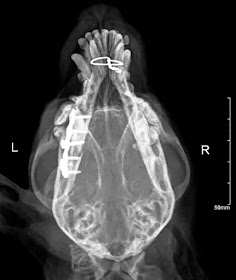

En esta ocasión tenemos un Bichón Maltés de 2,5 kg, que ha sido atropellado y presenta una fractura de mandíbula. Veamos las radiografías previas:

Generalmente, en esta vista, aunque se sospecha de fractura, no pueden apreciarse todos los detalles particulares, y suelen ser necesarias vistas oblicuas de las zonas donde se palpa desplazamiento para comprender mejor las fracturas del paciente.

El paciente presenta una fractura de la rama mandibular derecha, junto con una fractura de la sínfisis mandibular. En la planificación operatoria, debemos considerar que aunque la fractura de la sínfisis mandibular es fácilmente solucionable, tenemos también una fractura de la rama mandibular bastante caudal, en un paciente muy pequeño y con muy poco hueso para anclar los implantes porque la mandíbula se estrecha mucho caudalmente.

Probablemente los tornillos normales no puedan sujetar lo suficiente la mandíbula a ese nivel, y tampoco lo lograríamos con fijadores externos, por lo tanto, fue necesario recurrir a tornillos bloqueados, en una mini placa de titanio.